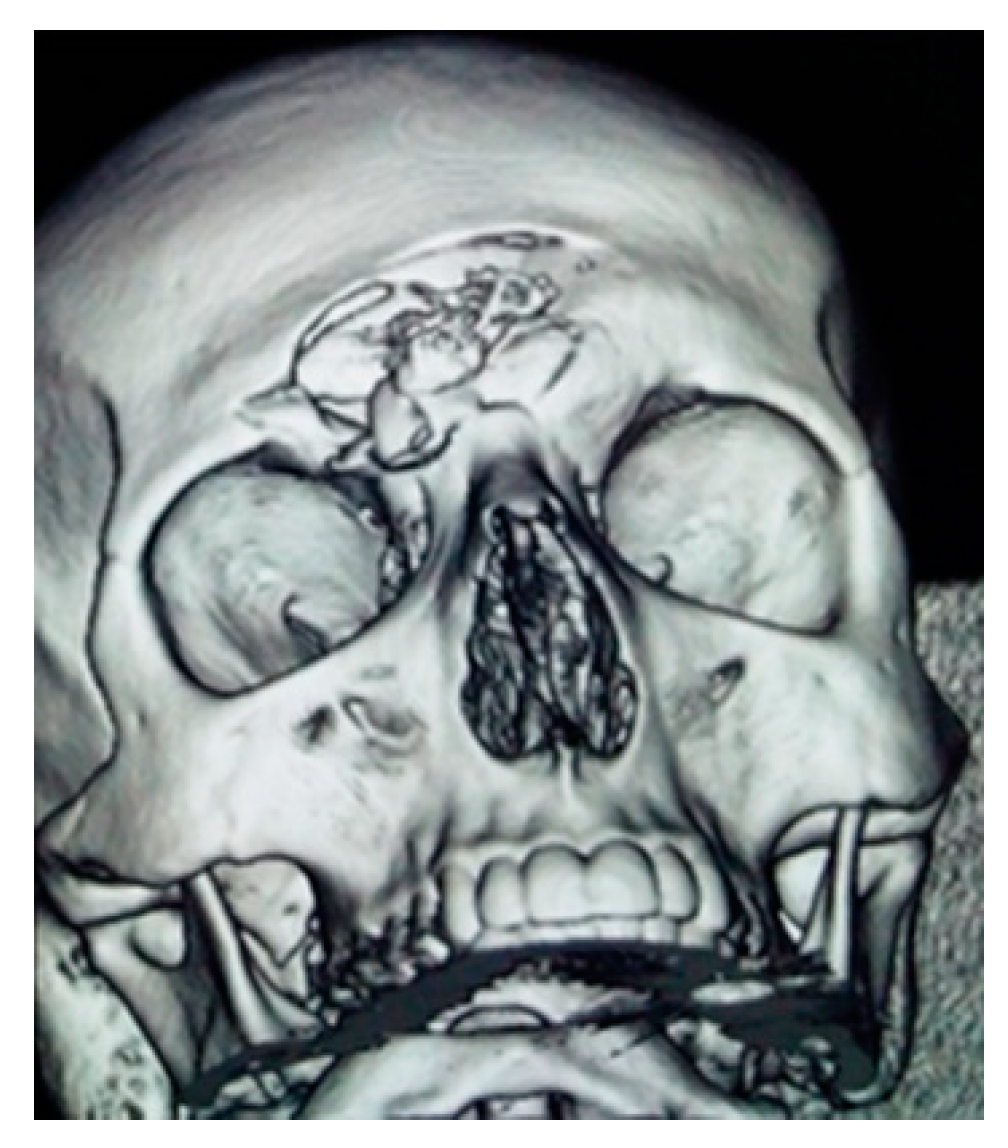

- Onișor-Gligor, F.; Țenț, P.A.; Bran, S.; Juncar, M. A Naso-Orbito-Ethmoid (NOE) Fracture Associated with Bilateral Anterior and Posterior Frontal Sinus Wall Fractures Caused by a Horse Kick—Case Report and Short Literature Review. Medicina 2019, 55, 731. [Google Scholar] [CrossRef]